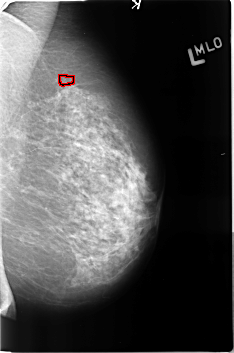

Digital Database for Screening Mammography

Volume: benign_04 Case: B-3361-1

B_3361_1.LEFT_MLO

LEFT_MLO LINES 4584 PIXELS_PER_LINE 3032 BITS_PER_PIXEL 12 RESOLUTION 50 OVERLAY

FILE: B_3361_1.LEFT_MLO.OVERLAY

TOTAL_ABNORMALITIES 1

ABNORMALITY 1

LESION_TYPE CALCIFICATION TYPE PUNCTATE DISTRIBUTION CLUSTERED

ASSESSMENT 4

SUBTLETY 3

PATHOLOGY BENIGN

TOTAL_OUTLINES 1

BOUNDARY